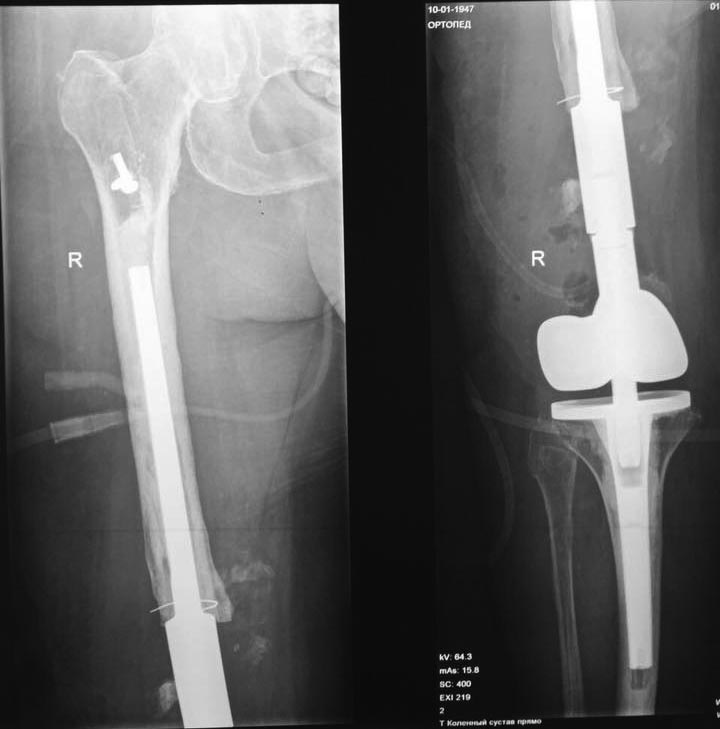

Зачастую после удаления Штифта мы ставим подобную пластину. А протез можно и после сращения поставить.

Гриш, ты прав... однако на твоем снимке нету жуткого артроза, как в данном случае.

Геворг, я пластину на снимке показал, тут вообще корригирующая была))

После удаления гвоздя я бы сделал костную пластику (декортикации будет маловато) и пластину, как выше показал Григорий. В Вашем случае я бы взял пластину на 2-3 отверстия длиннее и на проксимальный ее части оставил бы свободными пару отверстий, если считать от перелома.

На самом деле случай интересен тем, что нужно постараться подобрать оптимальный баланс, ведь перелом на фоне остеопороза требует относительной стабильности, а ложный сустав - абсолютной. Хороший случай.

Попытка же выполнить эндопротезирование здесь чревата целым сонмом осложнений. Поэтому, мне кажется, сначала лечим перелом, а уж потом разговариваем с пациентом об этой перспективе.

UPD. И да, дистальный конец гвоздя можно и не удалять. Винты только.

Пластина - хороший вариант. Может, даже double plating будет здесь в самый раз

Иван, и ещё один плюс делать в два этапа: можно спокойно идти на укорочение, затем после сращения и удаления пластины на протезе за счёт вкладыша нивелируешь укорочения

Еще раз смотрю на снимки - здесь практически диафизарный псевдатртроз. На вид не самый бесперспективный. Онкологический протез тут - из пушки по воробьям. Можно даже сделать остеосинтез, и в эту же сессию, или с отсрочкой, не дожидаясь сращения - стандартное эндопротезирование.

Мне кажется, удаление металлоконструкций, резекция ложного сустава с декортикацией, остеоперфорацией и реостеосинтез дистальной бедренной пластиной или DCS. Как предложил д-о Григорий Карапетян. Можно попробовать дистальный гвоздь. Но только со спиральным клинком, толстый с разсверливанием

Дистально-латеральная LCP пластина + костной пластика сделают своё дело.